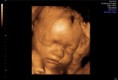

Fotogaléria: Postnatálny vývin